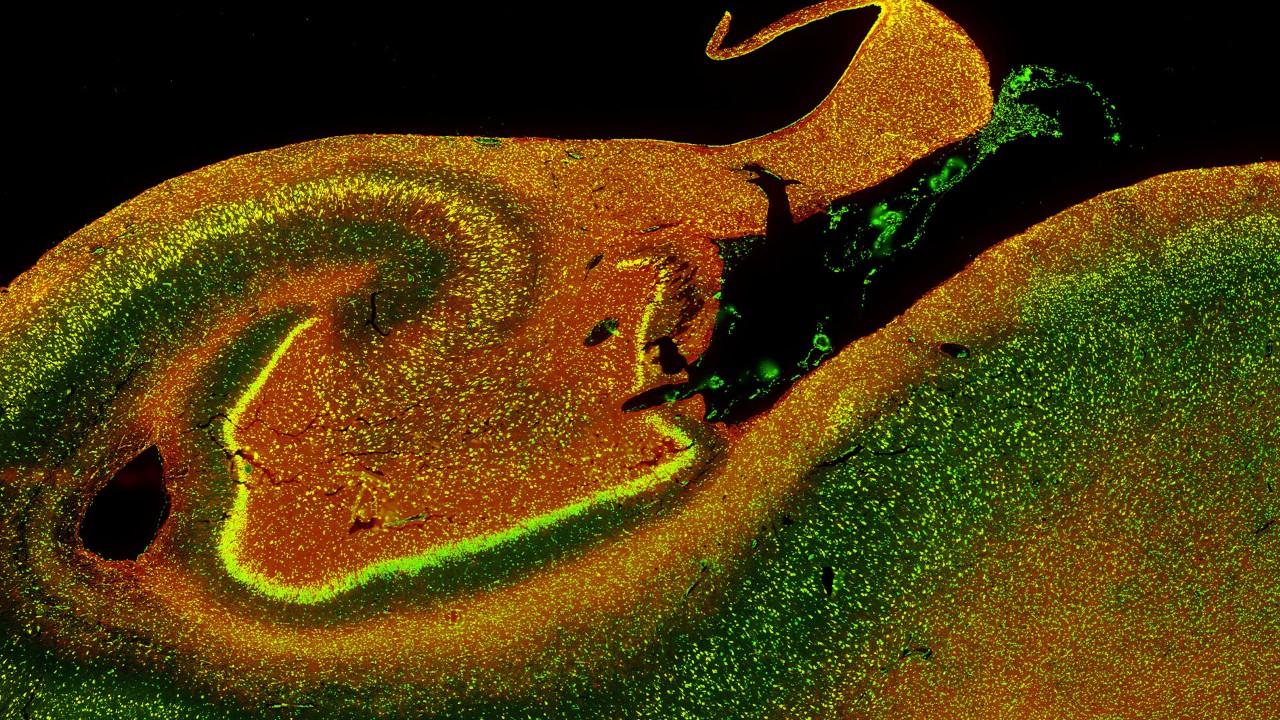

图片来源:Bruker Spatial Biology。

使用 CosMx Whole Transcriptome 面板绘制的人脑海马体图像(将于 2025 年上市)。 图片由 Bruker Spatial Biology 提供。